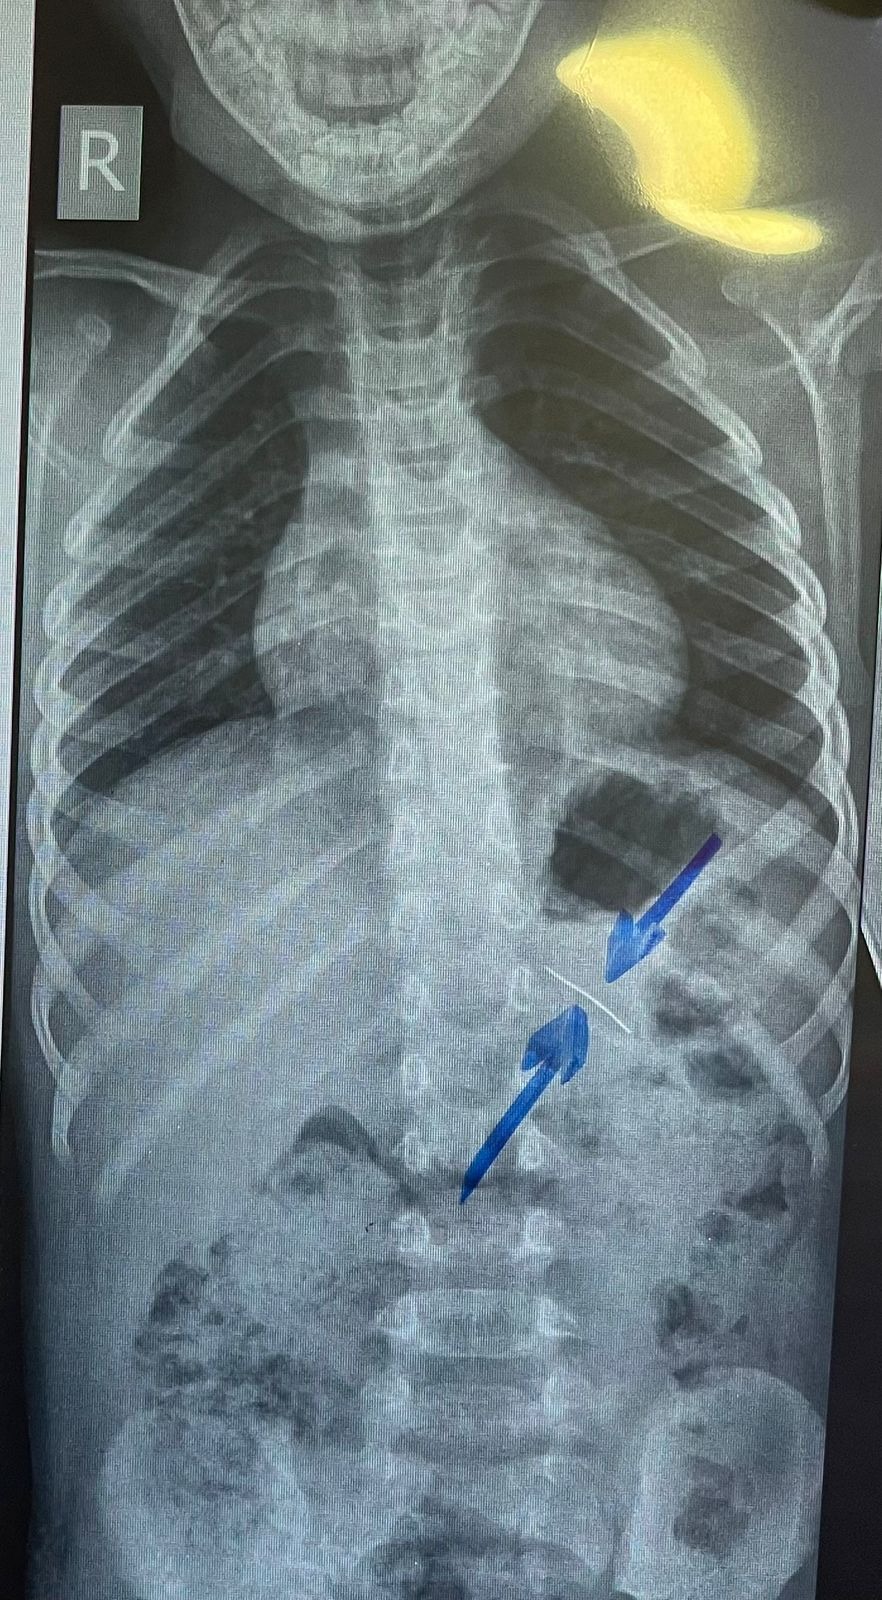

نجح فريق طبي من وحدة أمراض الجهاز الهضمي والكبد ومناظير الأطفال بقسم طب الأطفال بمستشفى سوهاج الجامعي في إجراء تدخل دقيق لاستخراج دبوس من معدة طفل يبلغ من العمر أربع سنوات، باستخدام منظار معدة خاص بالأطفال، دون حدوث أي مضاعفات، وقد غادر الطفل المستشفى بعد ثلاث ساعات فقط من الإجراء، وهو في حالة صحية جيدة.

وأكد الدكتور أحمد كمال، المدير التنفيذي للمستشفيات الجامعية ، أن التعامل مع الحالة تم بسرعة وكفاءة، حيث تمكن الفريق الطبي من استخدام المنظار الخاص بالأطفال لاستخراج الدبوس دون أي تدخل جراحي، مما ساهم في خروج الطفل من المستشفى في نفس اليوم بحالة ممتازة.